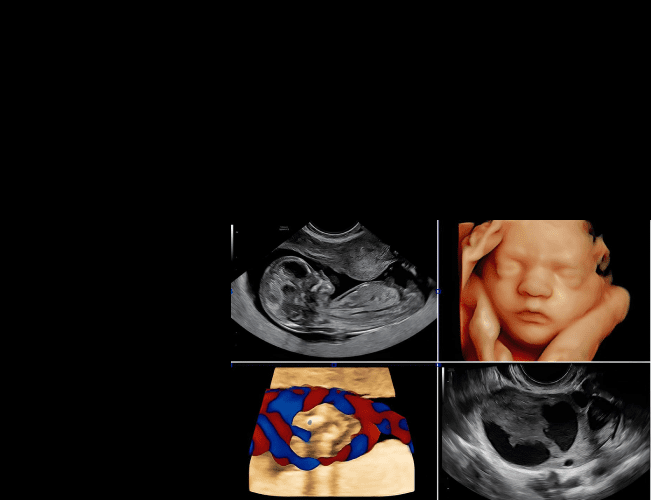

Функція Fetal HS™

Спрощує оцінку серця плода, надаючи поетапний алгоритм, який використовує штучний інтелект для визначення положення плода та нормальної анатомії серця плода за допомогою зображень чотирьох камер серця, трьох судин та вісі серця.

Spine Trace

Просо та легко отримуйте складні 3D зрізи. Просто намалюйте хребет, і система автоматично створить коронарний зріз.

Flow Profiles

Швидко та зручно оптимізує кольоровий та імпульсно-хвильовий допплер.